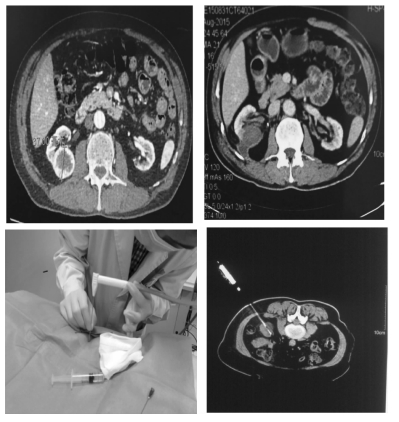

事实上,权威数据提示20%影像学上恶性表现的早期小肾“癌”(T1a)病理结果为良性。因此对于早期肾癌,业内专家已就其治疗最终目标达成共识,包括肿瘤特异性生存、肾功能的保护、减少治疗相关死亡率,以及患者的术后生存质量,尽管存在争议并依赖于基础的肾功能状态,但热缺血时间超过30分钟可能造成的肾脏不可逆缺血后损伤已经成为泌尿外科医生都在遵循的标准。因此无需血管阻断、更加微创、对肾功能影响极小的原位肿瘤冷冻消融的应用逐渐得到拓展,尤其是冷冻消融术。20世纪90年代,根据物理学Joule-Thompson原理应用氩气和氦气(俗称“氩氦刀”)标志着现代冷冻技术的开始,细冷冻“刀头”使直接经皮穿刺成为可能。可采用局部麻醉下B超或CT引导下肾癌冷冻消融术(见下图)。均采用降温复温两循环,耗时30分钟。

肾肿瘤冷冻消融术风险小、恢复快,为一般情况差、并发症多、孤立肾肿瘤及畏惧切除性手术等部分肾肿瘤患者提供了理想的保肾治疗选择。